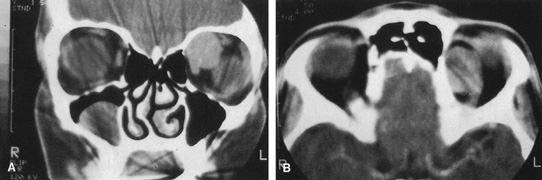

Procedure

A frontoethmoidal, or Lynch, skin incision is marked halfway between the medial canthus and bridge of the nose. It extends superiorly and inferiorly in a curved fashion approximately 2 to 3 cm (Fig. 16). The exact limits of the incision depend on the location of the underlying lesion. Injection of local anesthetic with epinephrine provides vasoconstriction, which greatly enhances hemostasis. After the skin is incised, a unipolar cutting cautery is used to extend the incision deeply to the periosteum. Bleeding may be encountered, especially in the area of the angular artery and vein. Exposure is enhanced with 4-0 silk sutures passed into the orbicularis muscle and clamped to the drapes.

Fig. 16. A. Patient with right orbital cellulitis. B. Coronal CT scan demonstrating subperiosteal abscess formation from frontal and ethmoidal sinusitis. C. Frontoethmoidal orbitotomy incision marked for abscess drainage.

The periosteum is exposed and incised with a Freer elevator and then is reflected off the bone posteriorly. It is generally quite adherent to the curved contour of the medial canthal bones, especially at the medial canthal tendon. The anterior lacrimal crest is encountered inferiorly. Care should be taken not to damage the lacrimal sac with the elevator. The posterior lacrimal crest is visible behind the sac. Adequate mobilization of the periosteal connections to the anterior lacrimal crest gives a large area of exposure. The periosteal elevation is carried superiorly in the area of the trochlea. Elevation of the periosteum opens the subperiosteal space. Blood or pus caused by fracture or infection, if present in this space, is encountered at this point.